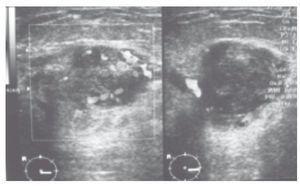

El ultrasonido mamario reporta un nódulo sólido muy vascularizado con márgenes definidos, que mide 3 x 2 cm, en la región del radio de las 6, línea "A" en la mama derecha, categoría BIRADS 4b (fig. 2).

Figura 2. Al ultrasonido se reporta nódulo bien definido con gran vascularidad en el Doppler. BIRADS 4.